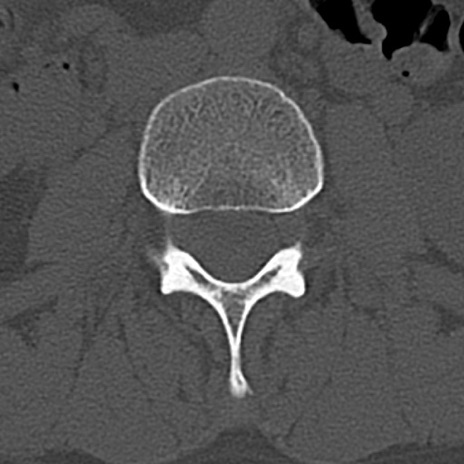

腰椎CT

横断像と矢状断像